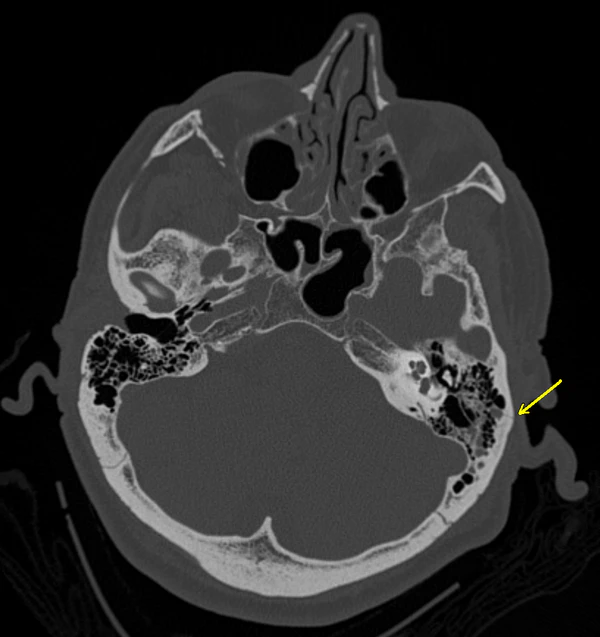

Симптом Бэттла (Бэттла признак) — кровоподтек (экхимоз) над сосцевидным отростком височной кости. Часто это единственный внешний признак базилярного (от лат. basilaris — основной, относящийся к основанию черепа) перелома черепа, чаще всего каменистой части височной кости.[1][2][3]

Признак Бэттла проявляется за одним или обоими ушами. Существуют определенные сложности для выявления данного симптома у больных с черепно-мозговой травмой. Его можно не заметить из-за волос. Кроме того, при оказании скорой медицинской помощи сразу после получения травмы данного симптома может не быть так как он обычно через 24-48 часов после перелома и может сохраняться в течение нескольких дней или недель.[4] При переломе костей черепа симптом Бэттла может сопровождаться гематомами вокруг глаз (симптом глаз енота), истечением ликвора из носа (ликворея), повреждением лицевого нерва, кровоизлиянием в полость среднего уха, а также угнетением сознания при тяжелой черепно-мозговой травме.[1]

Приложение достаточно большого усилия для перелома основания черепа вызывает появление кровоподтеков в области сосцевидного отростка из-за повреждения прилегающих к нему тканей. Также признак Бэттла может проявиться вследствие поступления крови из места перелома в область сосцевидного отростка.[8]